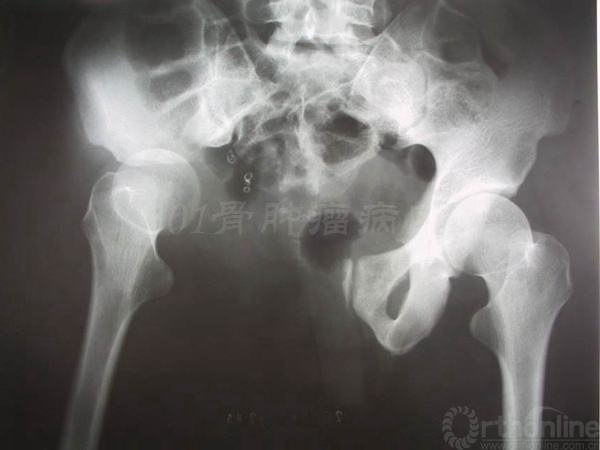

患者女性,术前X片提示:左侧骨盆Ⅱ+Ⅲ区溶骨性改变,诊断考虑骨巨细胞瘤合并动脉瘤样骨囊肿。血管栓塞后行骨盆Ⅱ+Ⅲ区切除,股骨头旷置术。术后病理报告是骨巨细胞瘤恶变,故行化疗6个月。术后13年随访,患者有跛行,但行走自如。

术前X线片